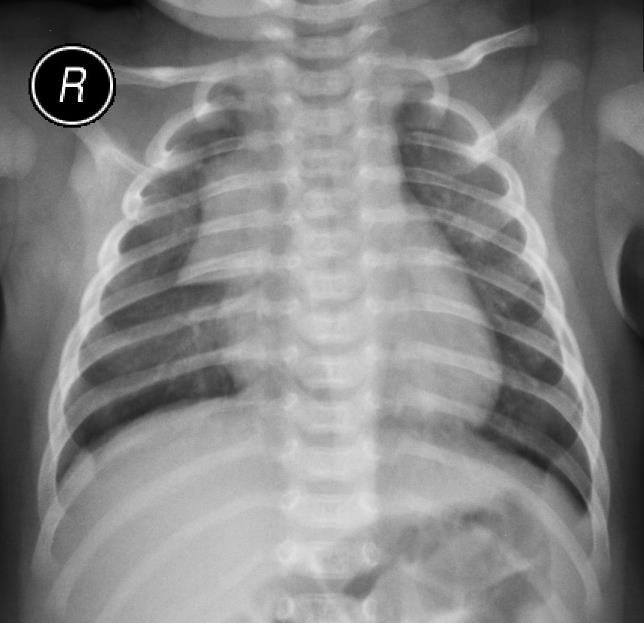

Pytanie 70

U 4-miesięcznego niemowlęcia z objawami nieżytu górnych dróg oddechowych i towarzyszącym pokaszliwaniem oraz ze stridorem wdechowym słyszalnym tylko w trakcie niepokoju, płaczu wykonano rtg kl. piersiowej, którego obraz zamieszczono poniżej. Jaka należy zinterpretować zacienienie górnego pola klatki piersiowej po stronie prawej?